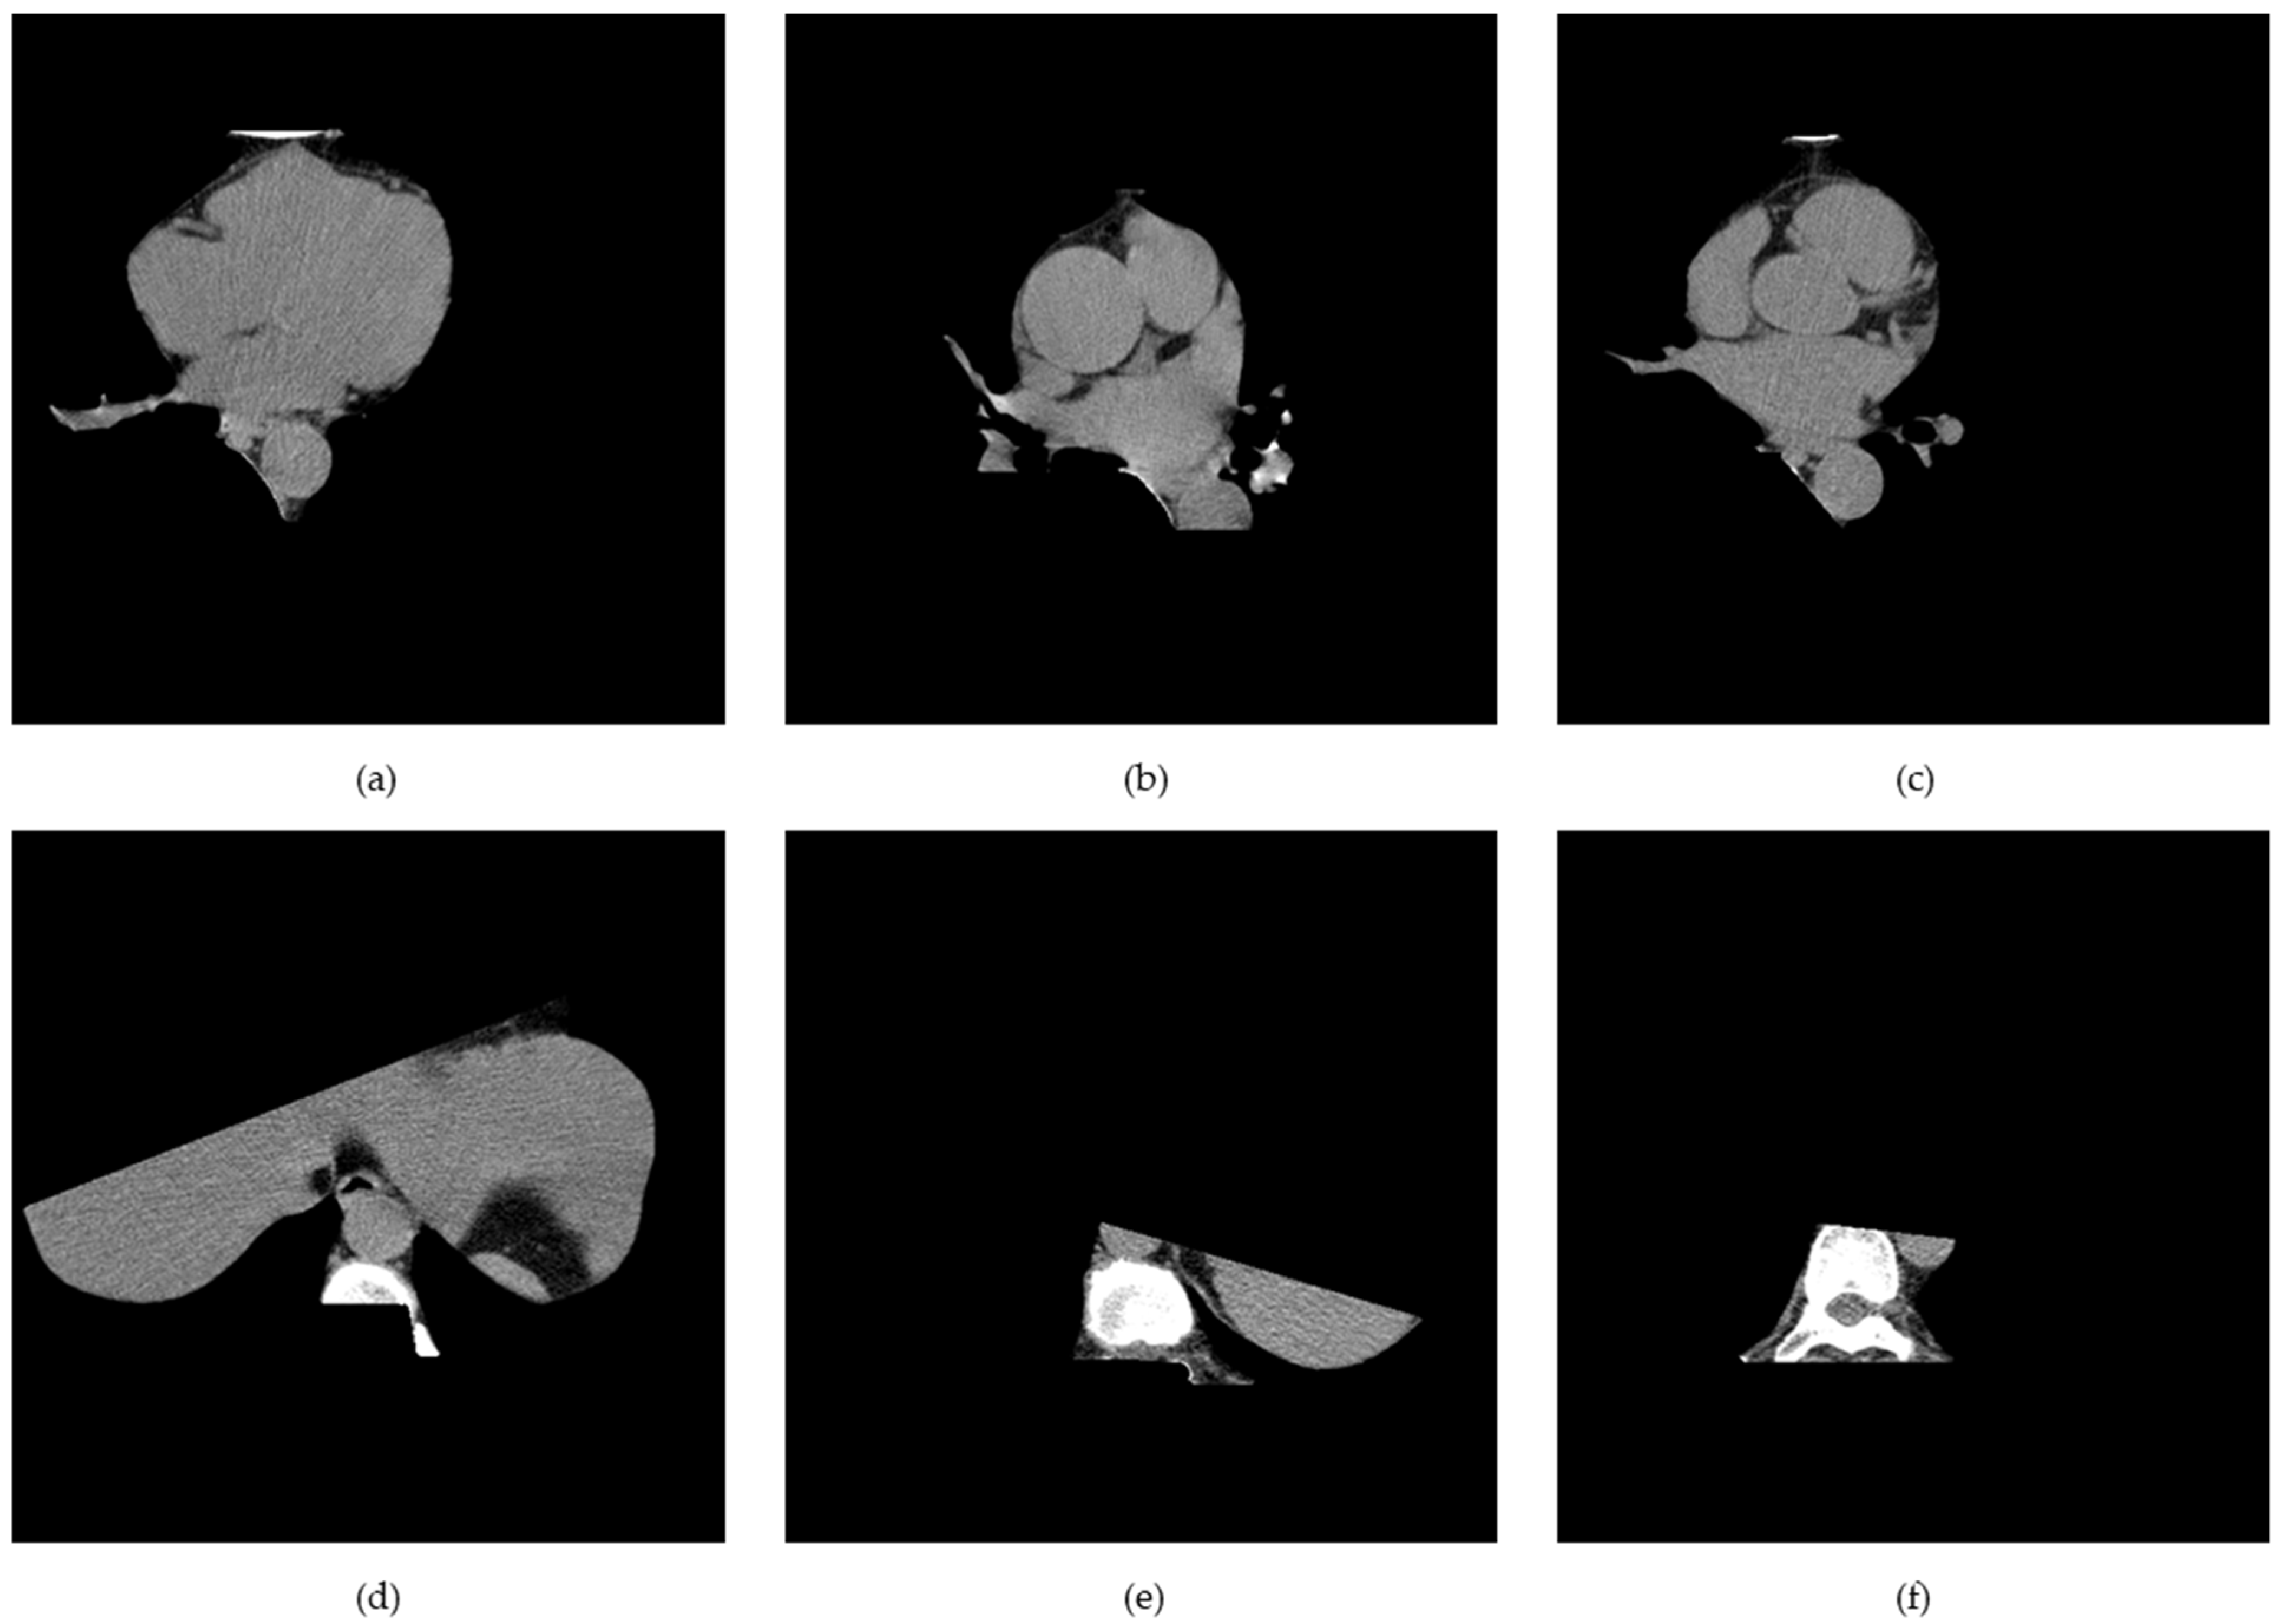

K-means clustering and the mathematical morphology were used to dissect the cardiac region to generate the cardiac segmented images. First, the air material at the edge of the coronary artery calcium score CT image was filtered by the convex hull of the foreground mask. Afterwards, other body organs, such as fat, muscle, and lungs, were processed by the convex hull of the lung mask. Finally, the vertebral part was filtered by the convex hull of the vertebral mask. Figure 6 shows the way in which the whole cardiac segmented images generation process was carried out. The segmentation process is intended to generate a binary mask of the entire cardiac anatomical ROI containing the four chambers, the coronary artery, and the DA. First, the air mass at the edge of the chest CT image is filtered by the convex hull of the foreground mask. Then other body material—such as lungs, muscle, and fat—are filtered by the convex envelope of the lung mask. Finally, the spinal material is filtered by the convex hull of the spinal mask [24]. Figure 7 shows the results of the segmentation process, and in this paper, unnecessary regions in the heart CT image were removed by applying this algorithm.

Figure 7.

(a–c) Heart, and (d–f) non-heart, obtained through the cardiac region segmentation algorithm.